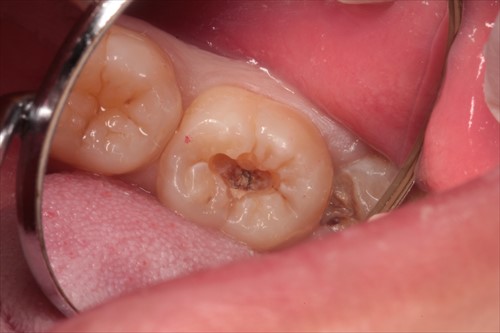

虫歯の写真です。歯の真ん中に黒い点があるだけです。

これだけならば一般の方は小さい虫歯としか思わないかもしれません。

しかしレントゲンで大きいという事は既に分かっています。

虫歯は入り口が狭く、中で大きく成長するものなのです。